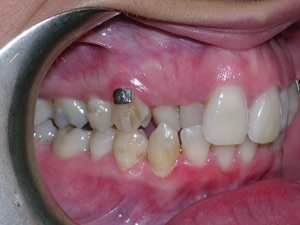

Now for the final results.

Needless to say, we were both quite happy with the outcome. Using elastics we were able to push back the back teeth and create space for the two teeth stuck behind.